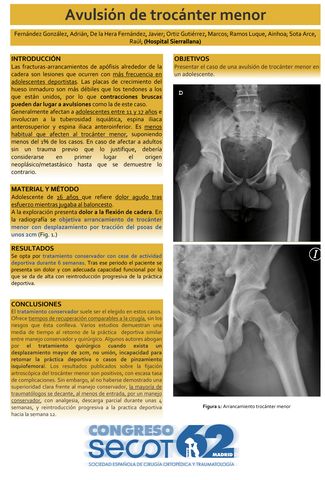

Avulsión de trocánter menor: a propósito de un caso

ADRIÁN FERNÁNDEZ GONZÁLEZ, JAVIER DE LA HERA FERNÁNDEZ, MARCOS ORTIZ GUTIÉRREZ, AINHOA RAMOS LUQUE, RAUL SOTA ARCE